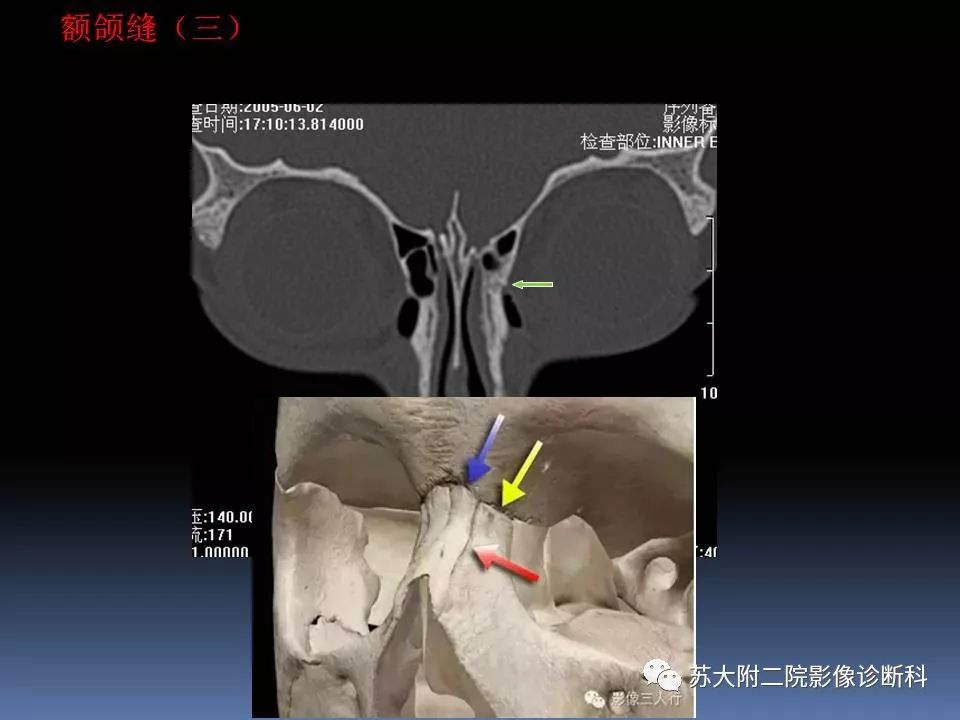

【PPT】鼻骨骨折影像诊断误区-3